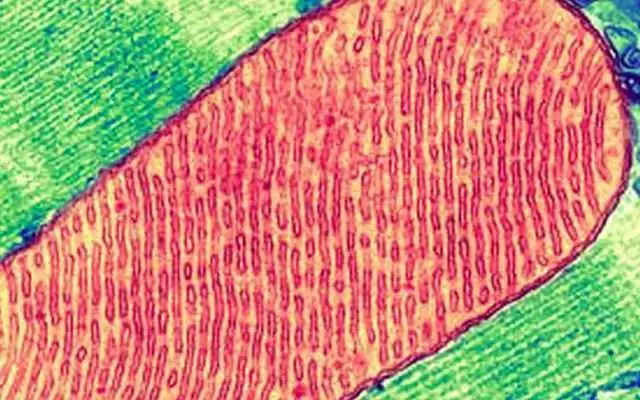

显微镜下的细胞内线粒体

越来越多证据支持代谢紊乱导致慢性疾病的原理,愈合周期的进程受细胞内线粒体和代谢因子控制。线粒体和代谢因子是新陈代谢产生的信号分子,包括100多个与愈合有关的细胞受体。代谢因子信号的异常导致细胞危险反应状态出现异常持续,出现愈合障碍。